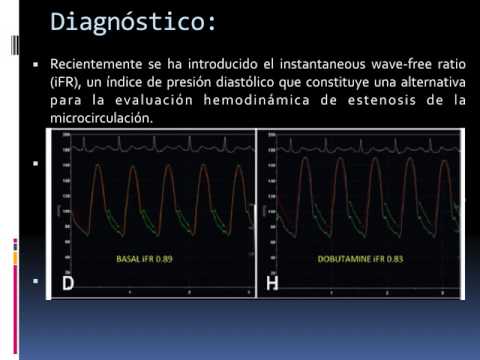

Impacto de la utilización rutinaria del estudio de la fisiología invasiva. Dra. María Eugenia Doppler. Residencia de Cardiología. Hospital C. Argerich. Buenos Aires